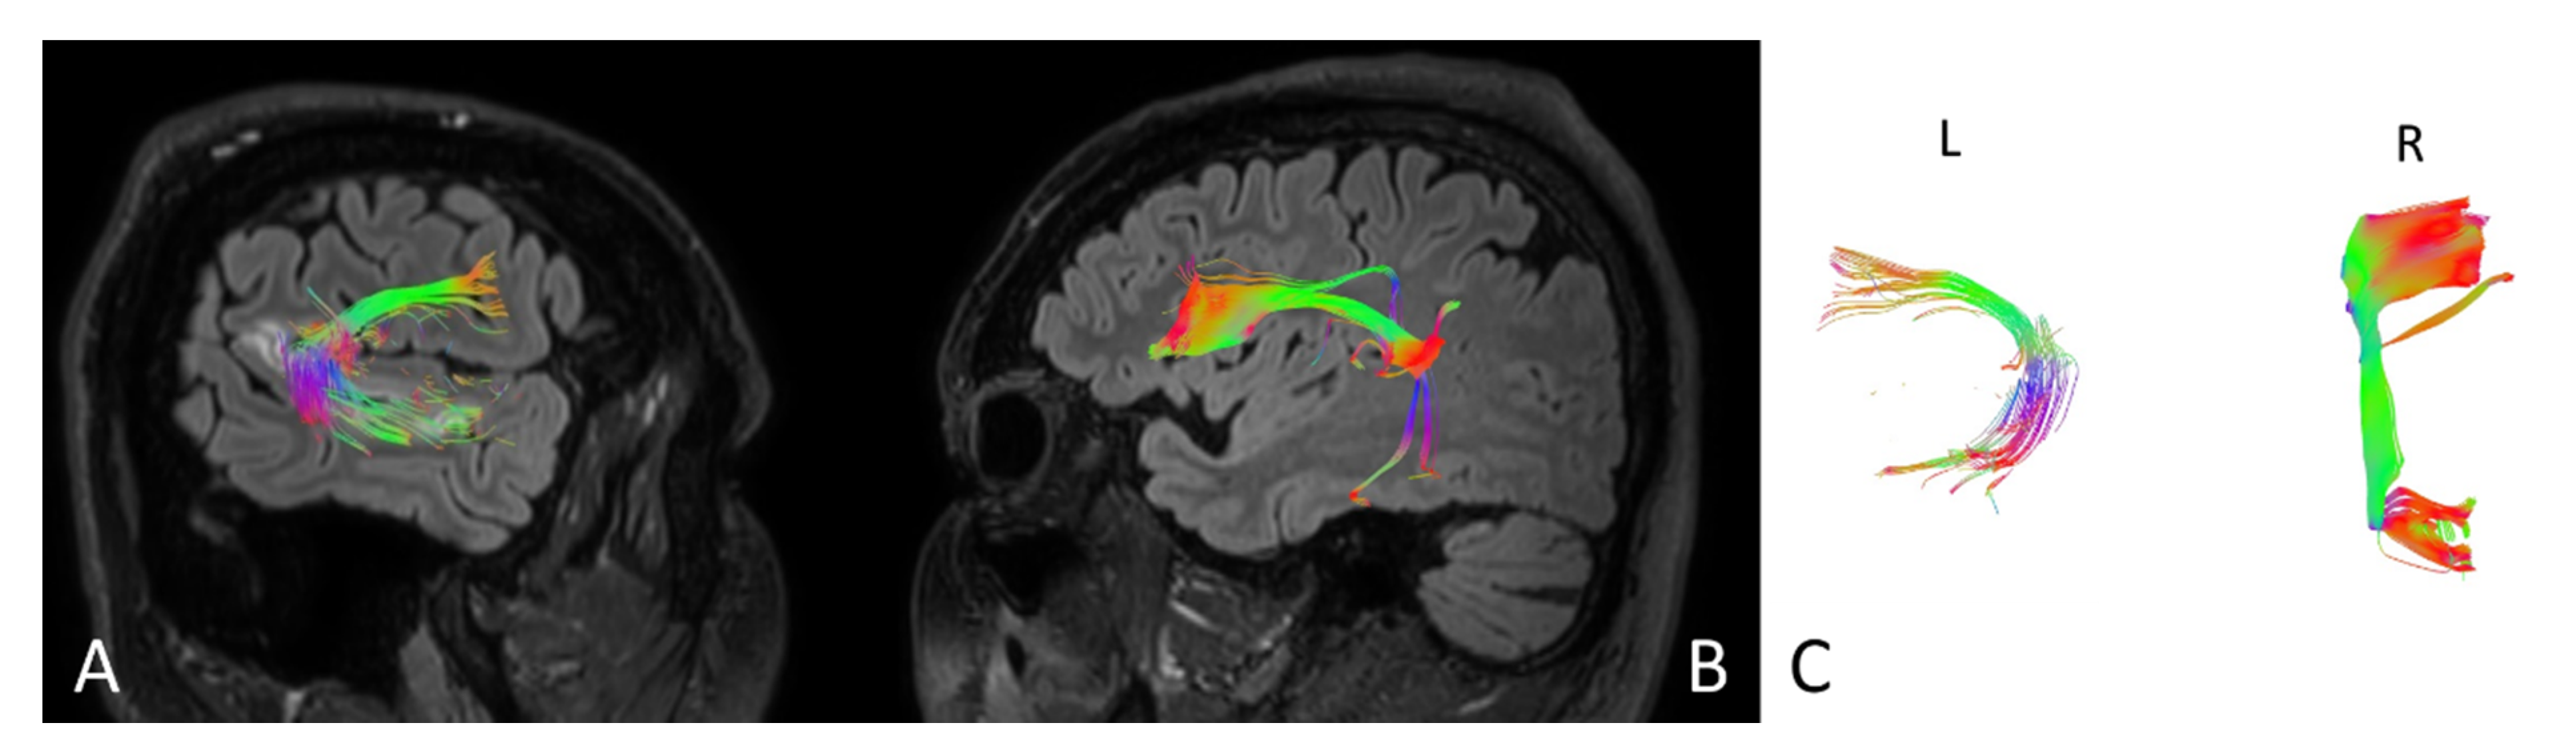

| Number of fibers | 148 | 183 | 155 | 152 |

| Volume of tract [mm2] | 13305 | 16440 | 14400 | 16338 |

| Length of tract [mm] | 88.5 | 98.3 | 87.5 | 97.1 |

| FA | 0.675 | 0.895 | 0.705 | 0.880 |